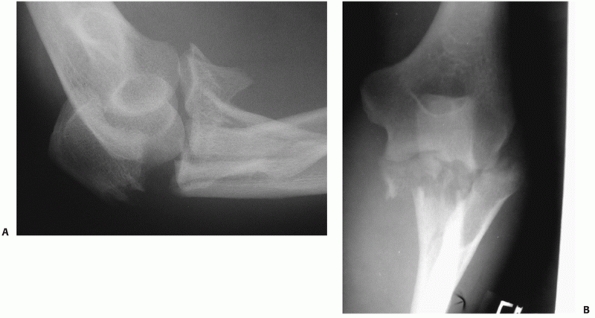

FIGURE 32-17 The so-called terrible triad of the elbow consists of dislocation of the elbow with fractures of the coronoid and radial head. A.

The coronoid fragment is the triangular fragment anterior to the trochlea. After manipulative reduction, this elbow could not be kept reduced despite cast immobilization. B. The coronoid fracture is a transverse fracture of the tip as seen on this three-dimensional computed tomography reconstruction. C. Operative fixation of the coronoid, replacement of the radial head, and reattachment of the lateral collateral ligament complex to the lateral epicondyle restored good elbow function. |

treatment: (i) Terrible triad injuries nearly always have a small

capsular attachment (Fig. 32-17B). Much less